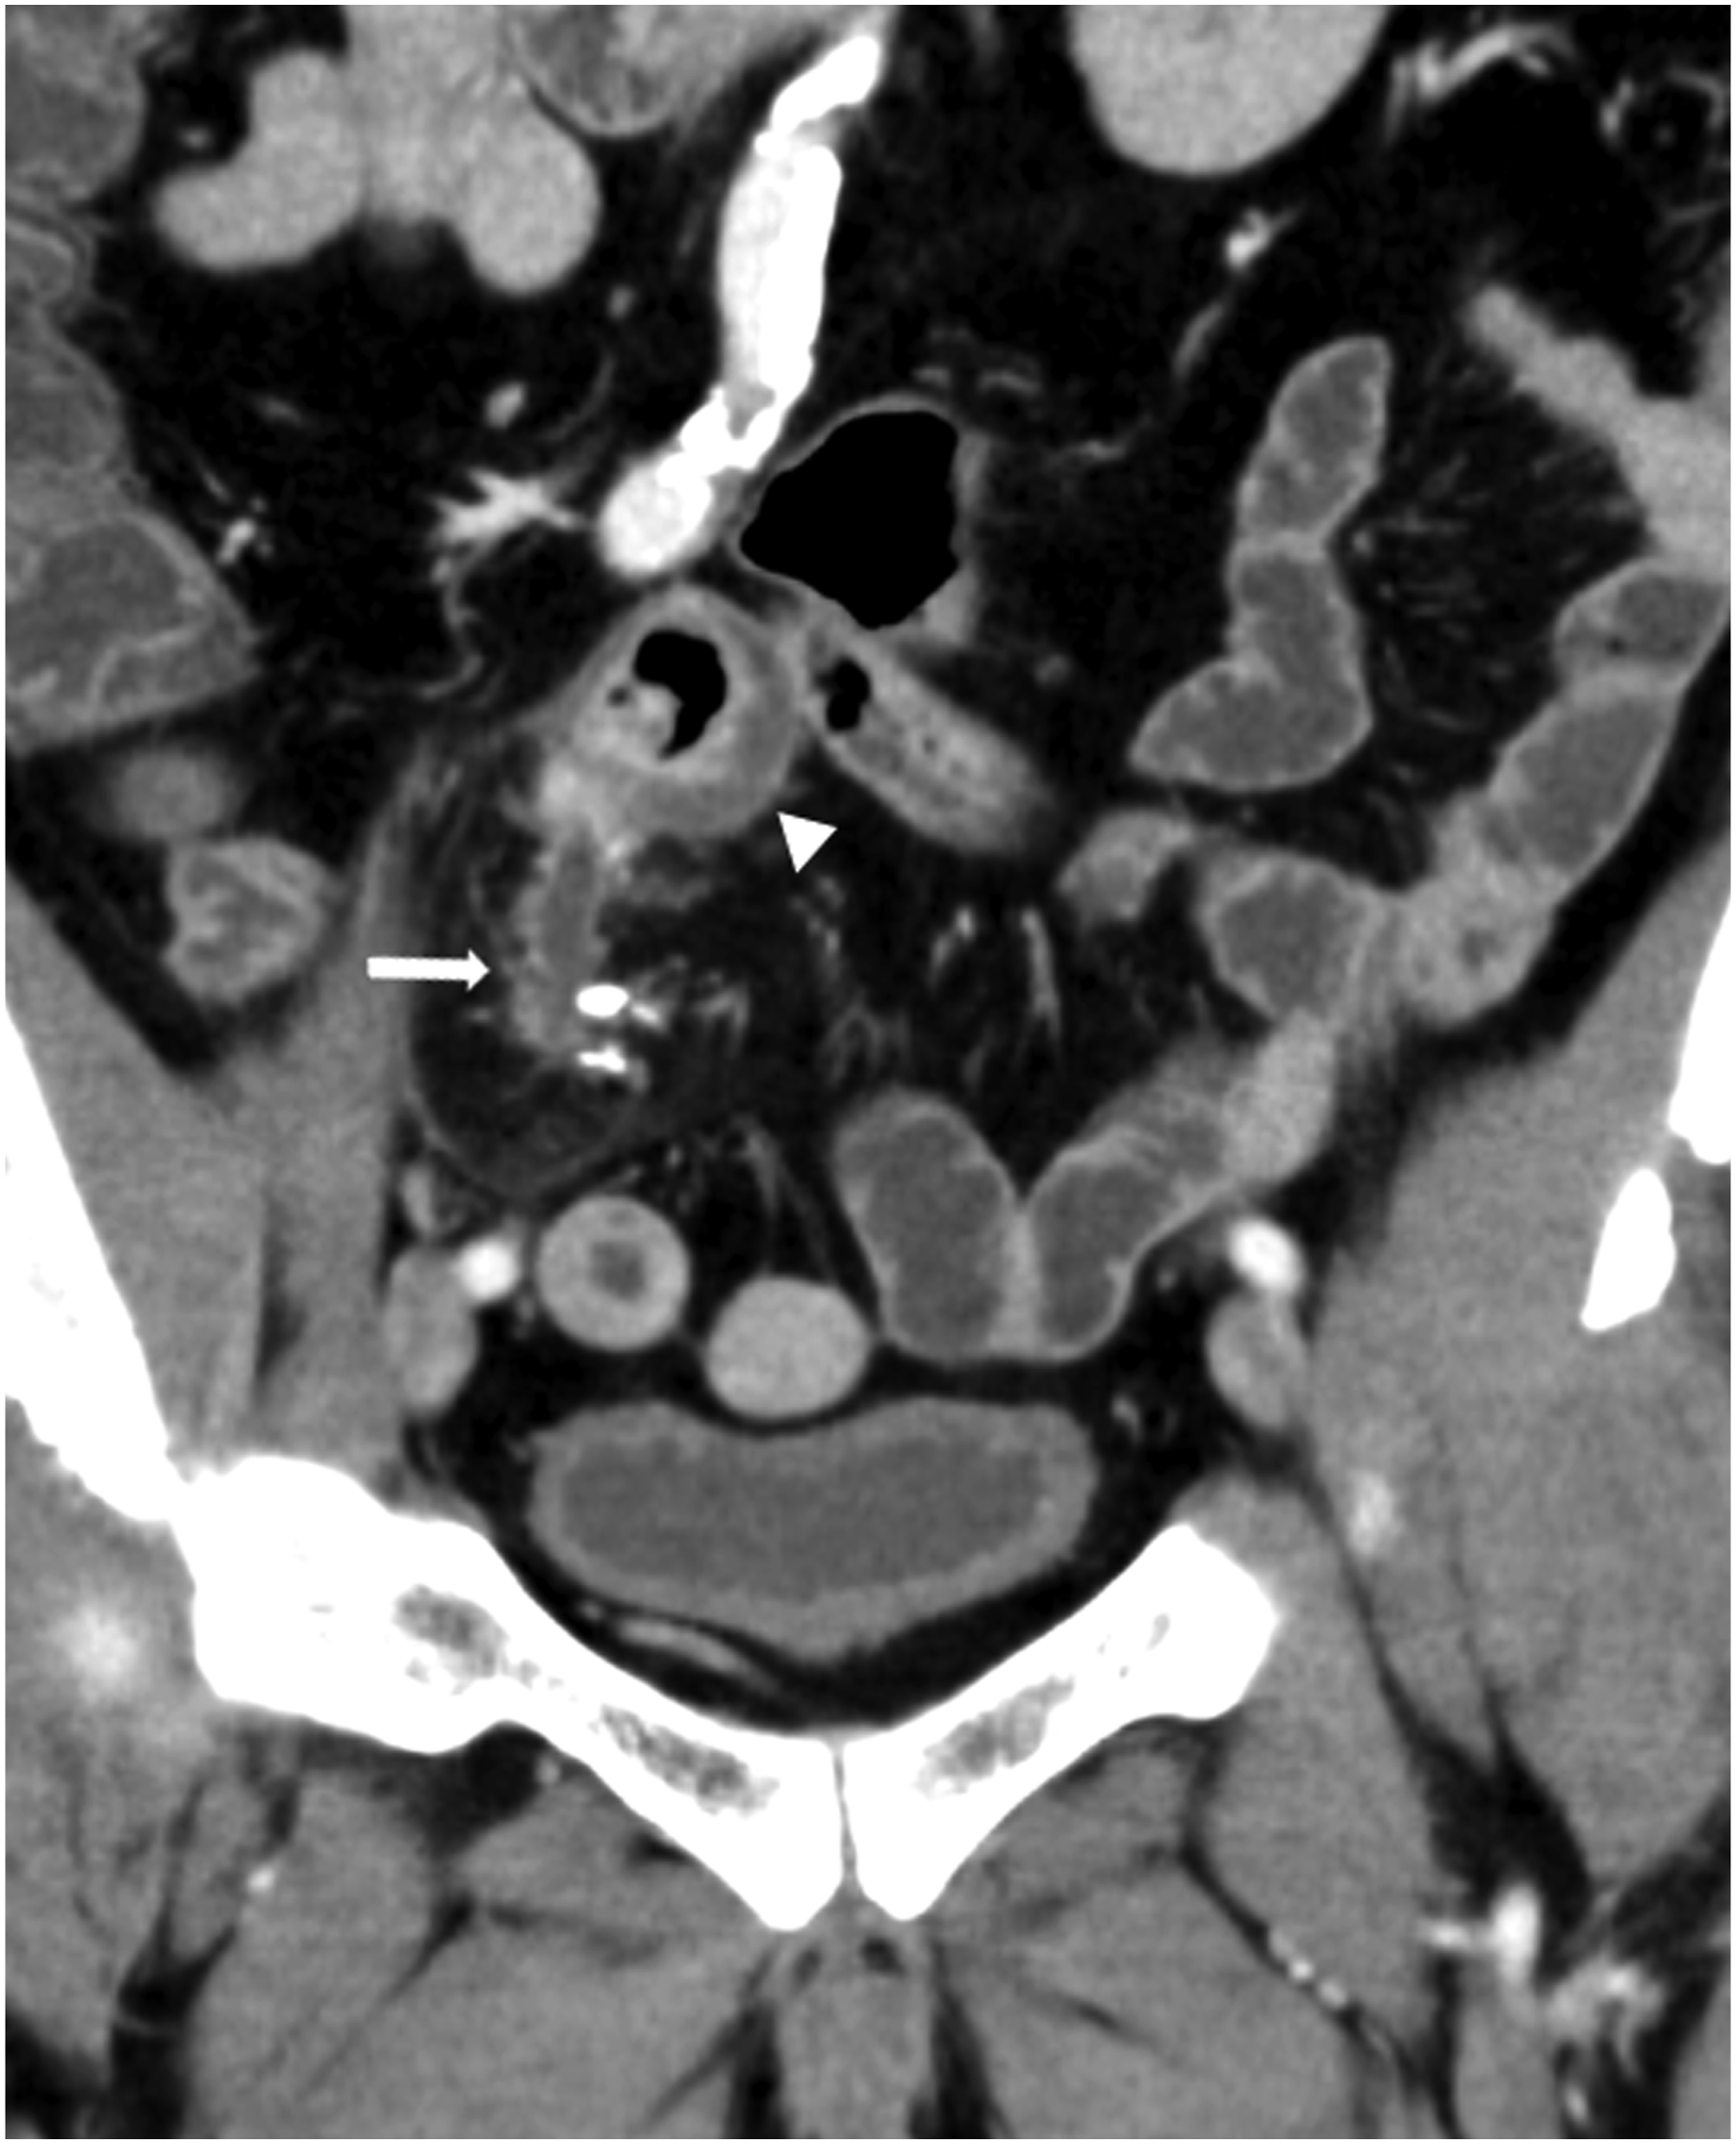

Contrast-enhanced CT was performed, revealing a luminal structure with calcification in the right lower abdomen and an increased fat concentration in the surrounding area, suggesting an acute inflammation (Figure 1, arrow). In addition, the adjacent intestine exhibited edematous wall thickening (Figure 1, arrowhead). We initially considered acute appendicitis, but given that this luminal structure branched from the small intestine and the appendix appeared normal, we ruled out acute appendicitis. Contrast-enhanced computed tomography (CT) image (coronal image, late phase). Luminal structures with calcification are observed in the right lower abdomen (arrow), and edematous wall thickening in the adjacent intestine (arrowhead).